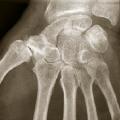

Rhizarthrose

ARTHROSE

POUCE